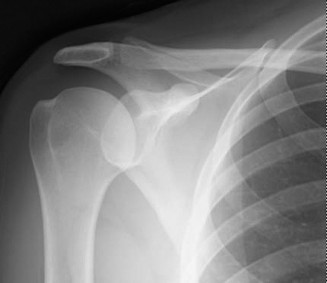

Rotator cuff tears are a common reason for shoulder pain and a common reason to obtain shoulder imaging. As a result, numerous different imaging modalities exist offering different pros and cons. Plain films are still the initial imaging modality of choice. These are most useful in ruling out other possible diagnosis but can help with the diagnosis of a rotator cuff tear as well. Changes to the tendon itself

may appear as calcific tendinosis, which would most commonly be seen at the bone–tendon interface. A decrease in the acromiohumeral distance (less than 2 mm) may also be indicative of a cuff tear. In late cases of rotator cuff tears, superior subluxation of the humerus may be evident. Certain variations in acromial anatomy, including spurs or a hook-shaped (type 3) acromions, may be associated with rotator cuff tears as well. With progression of rotator cuff tears, degenerative changes including spurs, cysts, and sclerosis may be evident at the greater tuberosity. In late, massive tears one may see degenerative changes consistent with rotator cuff arthropathy.

Shoulder CT scans (Answer A) are not typically used to diagnose rotator cuff tears. X-rays, aka roentgenograms (Answer C), can show signs of rotator cuff pathology but are not diagnostic. Some signs of chronic rotator cuff tears that are sometimes seen on AP view x-rays include calcific tendonitis, calcification of the coracohumeral ligament, proximal migration of the humerus, and cystic changes of the greater tuberosity. An outlet view x-ray can show a type III (hooked) acromion, which is correlated with a higher rate of rotator cuff tears, or an OS acromiale, which would require special consideration for surgical treatment. Shoulder arthrograms (Answer D) are used primarily only when MRI is contraindicated and are considered positive for a rotator cuff tear if dye leaks from the glenohumeral joint into the subacromial space. MR arthrogram (Answer E) has been shown to have equivalent diagnostic ability compared with standard MRI and can be used to diagnose rotator cuff tears. However, it adds an additional step and cost to a standard MRI, and it does not offer any additional diagnostic benefit for rotator cuff pathology. Therefore, standard MRI is preferred to MR arthrogram.